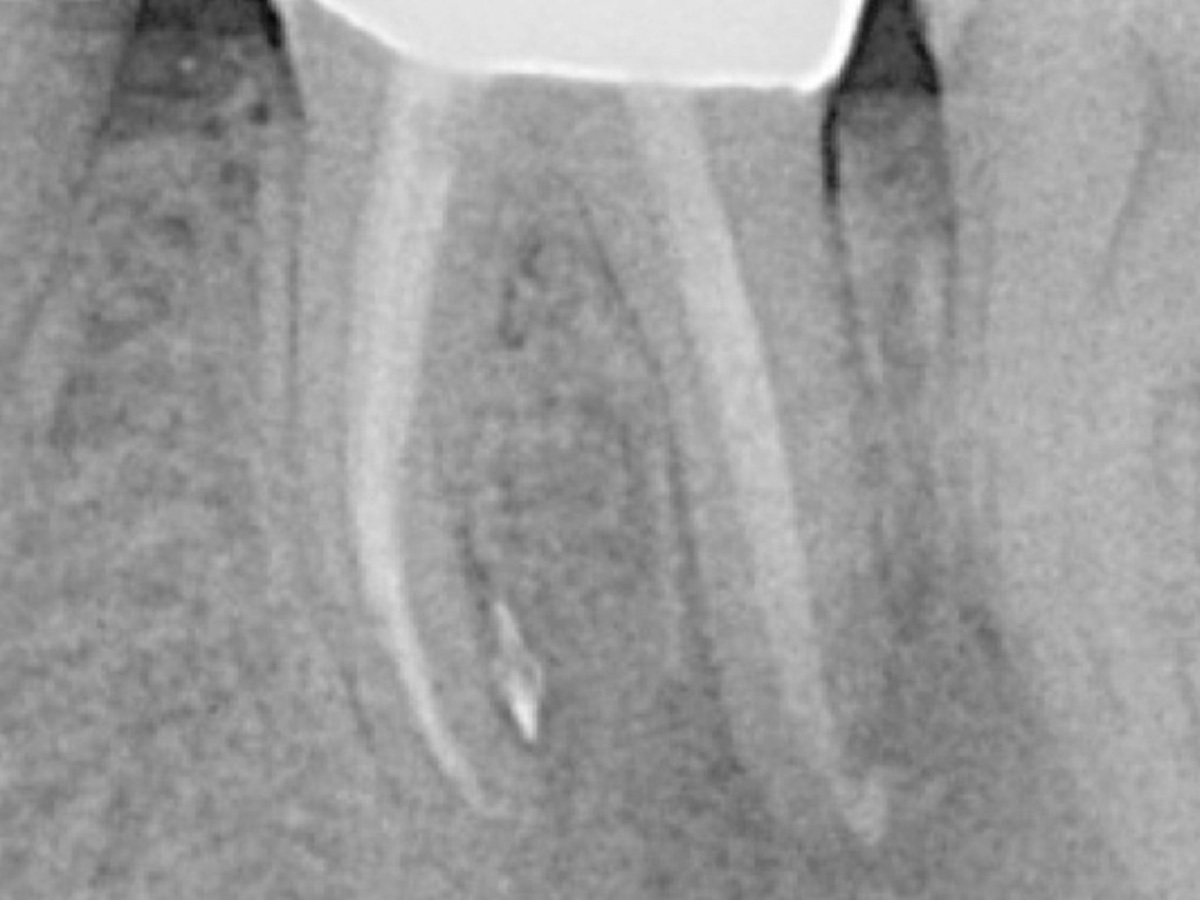

Sie erlernen die grundlegenden Bausteine eines evidenzbasierten endodontischen Behandlungskonzepts, welches langfristigenBehandlungserfolg garantiert.

• Moderne endodontische Diagnostik

• Biologische und mechanische Voraussetzungen für eine erfolgreiche Aufbereitung von Wurzelkanalsystemen

• 3D-basierte Planung der idealen endodontischen Zugangskavität und adäquaten minimalinvasiven Aufbereitung

• Techniken zur Bestimmung der idealen Arbeitslänge und Aufbereitungsgröße